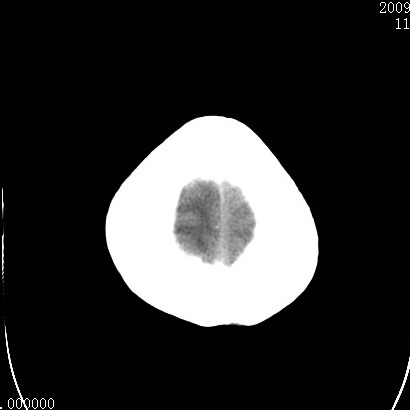

以下是引用余辉在2009-4-9 17:34:00的发言:[br]双侧脑白质对称性弥漫性密度减低,脑室脑沟裂池变小,双侧豆状核对称低密度,脑干对称性低密度,考虑1中毒性脑病2电解质异常(低钾钠等)3代谢异常及维缺乏等,进一步检查。